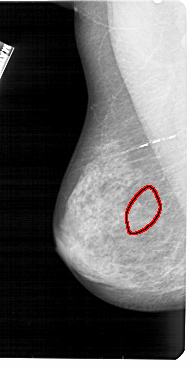

FILE: A_1393_1.LEFT_CC.OVERLAY

TOTAL_ABNORMALITIES 1

ABNORMALITY 1

LESION_TYPE CALCIFICATION TYPE AMORPHOUS DISTRIBUTION SEGMENTAL

ASSESSMENT 4

SUBTLETY 2

PATHOLOGY BENIGN

TOTAL_OUTLINES 1

BOUNDARY